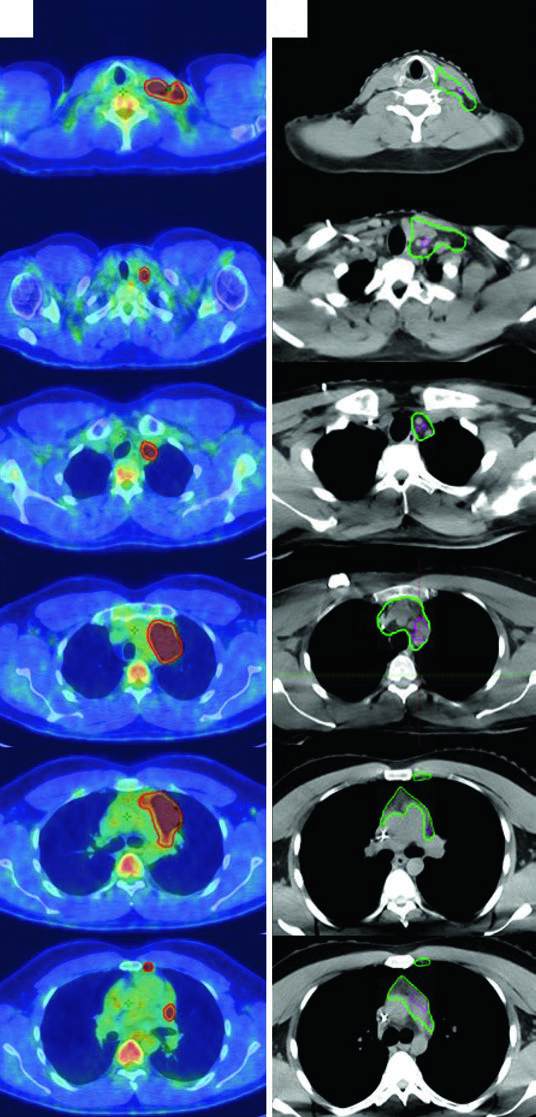

CT simulation and 4D-CT MIP axial slices showing CTV and ITV for diffuse gastric MALT lymphoma with perigastric involvement

Figure 31.6 — Gastric MALT lymphoma: ISRT CTV (red) and ITV (green) with 4D-CT MIP. Source: Target Volume Delineation and Field Setup, 2nd Edition

3DCRT and IMRT are recommended to spare kidney and liver. Suggested target volumes for extranodal lymphoma sites are detailed in the table below.

In practice, the 2 cm PTV margin for gastric lymphoma may not be adequate in some patients — stomach motion varies considerably, and the 4D-CT assessment is critical for determining the appropriate expansion.

Pre-operative and simulation CT axial slices showing ISRT CTV for sinonasal DLBCL involving ethmoid, sphenoid, maxillary, and frontal sinuses

Figure 31.8 — Sinonasal DLBCL: ISRT CTV (red) covering all involved sinuses after R-CHOP and near-total resection. Source: Target Volume Delineation and Field Setup, 2nd Edition

The illustrative case is a 56-year-old woman with stage IAE DLBCL of the left ethmoid/sphenoid sinus, extending across the nasal septum into the right nasal cavity, with cribriform plate erosion superiorly, left medial orbital wall erosion laterally, and left maxillary sinus extension inferiorly. The left frontal sinus was completely opacified. After near-total resection and 3 cycles of R-CHOP, consolidation RT was delivered with ISRT CTV covering the entirety of the involved sinuses. The delineation approach for nasal cavity and paranasal sinus tumors follows similar principles.